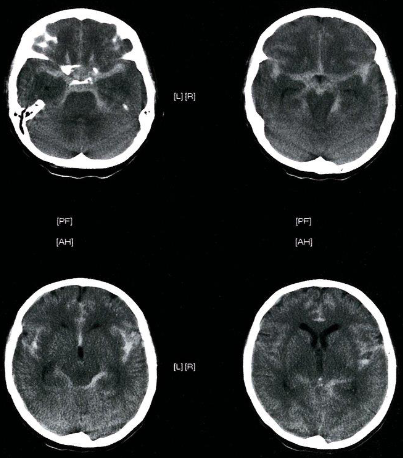

CT Brain IN EMERGENCY

Epidural hematoma

- Convex inner margin (lens-shaped)

- High density area

CT brain - Acute subdural hemorrhage

- crescent shape

CT brain - Chronic subdural hemorrhage

- Concave

CT brain - Acute on chronic subdural hematoma

- Inner margins are concave

A. Imaging study. *CT head *(without contrast; axial plane)

B. What is the most likely diagnosis? Subarachnoid hemorrhage

- Multiple areas of high attenuation in the basal cisterns, Sylvian fissures, and sulci are

- characteristic of extensive subarachnoid hemorrhage.

Intra ventricular hemorrhage

- Anterior/Posterior Horns hemorrhages

- 3rd ventricles

Subacute subdural hematoma

- Shifting + Isodensity ~~ SOL

Intracerebral hemorrhage

Infarction appear hypodense on CT without contrast

Sign? Hyperdense sign in stroke; LT Middle cerebral artery hyperintense

Y

Dense basilar artery and middle cerebral arteries on CT

Thrombus in vessel is hyperdense relative to flowing blood